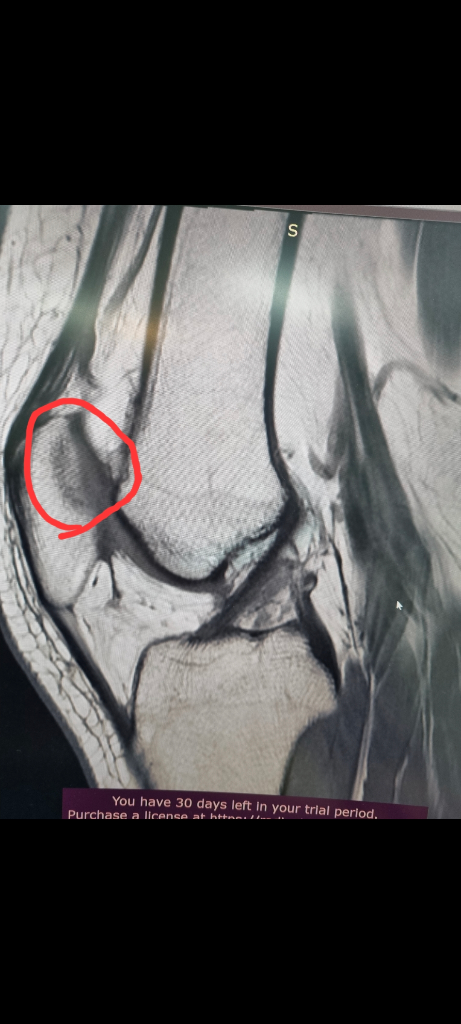

1. 추벽이 아닙니다.

2. 슬개골 관절면에 외상으로 인한 골수부종입니다.

3. 관절면 손상여부는 첨부해주신 영상만으로 알 수 없습니다